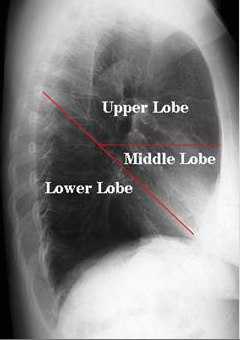

Представлена рентгенограмма правого лёгкого в боковой проекции с указанием топографии междолевых щелей.

В каждом лёгком различают доли, разделенные глубокими щелями. Правое лёгкое состоит из трёх долей, левое — из двух. На правую верхнюю долю приходится 20% лёгочной ткани, на среднюю — 8%, правую нижнюю — 25%, левую верхнюю — 23%, левую нижнюю — 24%.

Главные междолевые щели проецируются справа и слева одинаково — от уровня остистого отростка 3 грудного позвонка они направляются косо вниз и вперед и пересекают 6 ребро у места перехода его костной части в хрящевую.

Дополнительная междолевая щель правого лёгкого проецируется на грудную клетку по ходу 4 ребра от средней подмышечной линии до грудины.

На рисунке обозначены: Upper Lobe — верхняя доля, Middle Lobe — средняя доля, Lower Lobe — нижняя доля

Верхняя доля

, lobus superior. Ее нижний край сзади находится на уровне 4-го ребра. Справа идет вперед почти параллельно четвертому ребру, а слева - доходит до костно-хрящевого соединения 6-го ребра. Рис. А, Рис. Б, Рис. В, Рис. Г.

Средняя доля (правого легкого)

, lobus medius (pulmonis dextri). Имеется только в правом легком. Расположена спереди от средней подмышечной линии в промежутке между четвертым и шестым ребрами. Рис. А, Рис. Б.

Нижняя доля

, lobus inferior. Расположена в задней части грудной клетки. Ее верхний край идет косо вниз от уровня четвертого ребра по околопозвоночной линии до места пересечения шестого ребра со среднеключичной линией. Рис. А, Рис. Б, Рис. В, Рис. Г.

Косая щель

, fissura obliqua. Лежит между верхней и нижней долями левого, верхней, средней и нижней - правого легкого. Проецируется от четвертого ребра по околопозвоночной линии до шестого - по среднеключичной. Рис. А, Рис. Б, Рис. В, Рис. Г.

Горизонтальная щель (правого легкого)

, fissura horizontalis (pulmonis dextri). Отделяет среднюю долю от верхней. Соответствует четвертому ребру. Рис. А, Рис. Б.